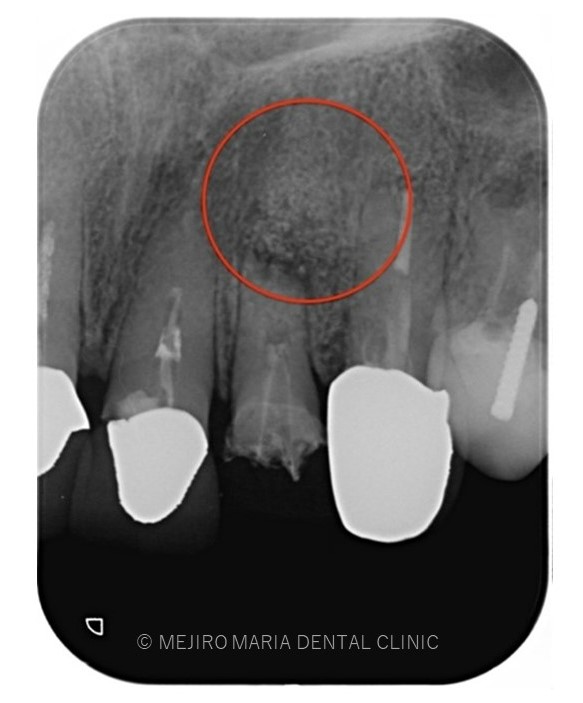

でのリカバリー_該当歯牙の精密根管治療後のレントゲン画像.jpg)

でのリカバリー_歯根端切除術後のレントゲン画像.jpg)

今回の症例は、他院にて歯根端切除術を行った根尖部(歯の根の先)に充填された人工骨の感染が原因と考えられます。

しかし、歯根端切除術の成功率は100%ではなく、多くの症例の中には少なからず再度オペを行うケースも出てくる可能性があります。

万が一、歯根端切除術が失敗した場合、人工骨の感染はより事態を悪化させることになります。

歯根端切除術後は術後の透過像で治癒を確認することが重要であり、感染が除去できていれば骨は患者自身の力で自然に再生を行うことになるので、人工骨を充填することはリスクが高い行為であると考えます。